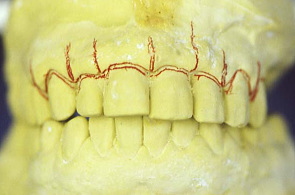

初診時の口の中の状態、歯ぐきは赤く腫れている。特に上の歯肉全体が浮腫して歯肉の締まりがなくなっている。